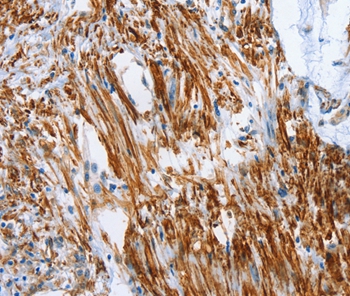

Immunohistochemical analysis of paraffin-embedded Human colon cancer tissue using #37340 at dilution 1/50.

Immunohistochemical analysis of paraffin-embedded Human cervical cancer tissue using #37340 at dilution 1/50.